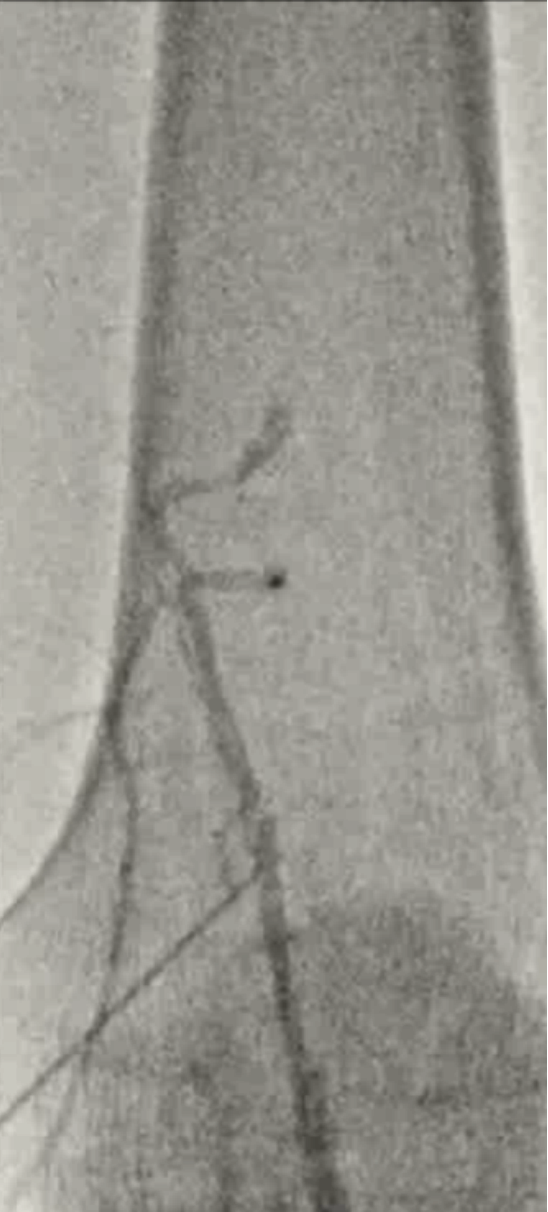

股浅动脉远端逆行入路

这是一种处理股浅动脉长段闭塞的备选方案——当正向开通失败时,从膝盖附近的远端血管反向穿刺来“接应”。

1. 适应症(什么时候用?)

· Proximal, Mid-SFA CTO:指股浅动脉近端或中段的慢性完全闭塞。

· 临床逻辑:当病变位于SFA中上段时,如果尝试从股动脉顺行穿刺无法通过闭塞段,就选择从膝盖上方的健康股浅动脉血管段逆向穿刺,绕过病变远端去完成手术。

2. 操作技术(怎么做?)

· Supine:平卧位。这是与经典腘动脉逆穿最大的区别。

· Medial thigh US/X-ray guided puncture:在股内侧,通过超声或X光透视引导下穿刺。

· 具体操作:患者平躺,腿稍外旋外展。在股浅动脉中下段内侧(避开股骨)穿刺股浅动脉远端或穿过收肌管的部位。通常首选超声引导看血流,造影辅助确认位置。